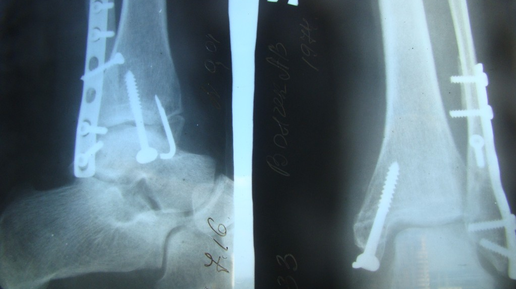

Основные виды переломов Вид перелома зависит от характера травмы, направление вектора силы действующей на скелет пострадавшего, и его положение в момент травмы закономерно указывает на характер перелома. Так при падении на вытянутую руку происходит перелом лучевой кости в типичном месте, при ударе бампером легковой машины, развивается характерный "бамперный перелом" и т.п. ПЕРЕЛОМЫ ЧЕЛЮСТИ Если пострадавший в сознании, посадить, наклонить немного вперед, приложить подушечку или сложенную в несколько слоев ткань, чтобы прижать челюсть (лучше, если это сделает сам пострадавший)...

Боль, отек покалывание в пальцах – все эти симптомы характерны для перелома запястья. Существуют разные типы травмы, из которых перелом Бартона – один из самых неприятных. Почему при таком переломе часто требуется операция и какие осложнения могут возникнуть после нее? Что такое перелом Бартона? Это болезненный перелом запястья со смещением, который вызывает отек и онемение, а также покалывание в кончиках пальцев. Подобный перелом происходит, когда вы падаете на согнутое запястье. В 70% случаев...